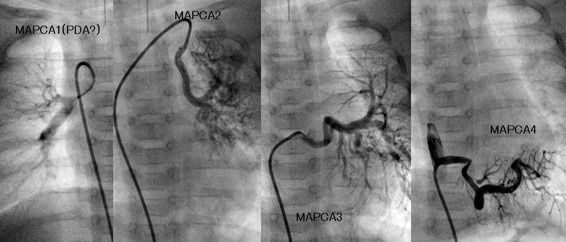

MAPCA症例 4本のMAPCAが有する症例

肺動脈統合術(unifocalizaton)術後 矢印の部分が狭窄病変

術後5ヵ月で肺動脈の狭窄に対してカテーテル治療を行った後の血管造影